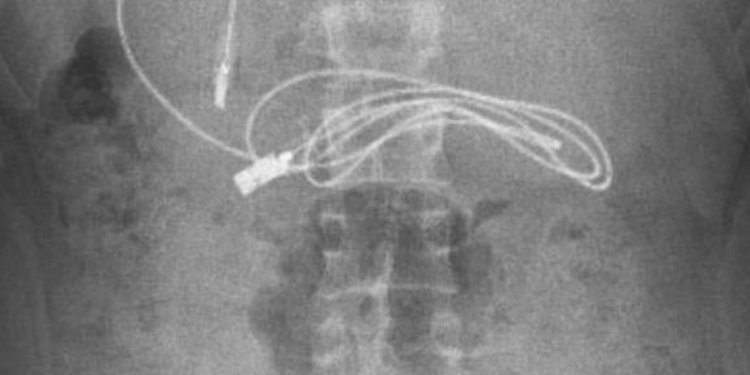

Diyarbakır'da 15 yaşındaki erkek çocuğunun midesinde tespit edilen 1 metrelik şarj kablosu ve toka başarılı bir endoskopi yöntemiyle çıkarıldı.

Diyarbakır’da kusma ve bulantı şikayetiyle hastaneye giden 15 yaşındaki erkek çocuğunun çekilen röntgeninde, midesinde şarj kablosu ve toka olduğu tespit edildi. Teşhisin ardından Fırat Üniversitesi’ne sevk edilen hastanın midesinden,  Çocuk Gastroenteroloji Hepatoloji ve Beslenme Bilim Dalı Başkanı Prof. Dr. Yaşar Doğan ve ekibi tarafından yapılan endoskopik işlemle  kablo ve toka başarıyla çıkarıldı.

KABLO İNCE BAĞIRSAĞA ULAŞTI

“Hastanın kusma ve karın ağrısı şikayetleri olması üzerine sağlık kuruluşuna başvurulmuş. Orada yapılan incelemelerde hastanın midesinde kablo tespit edilmesi üzerine bize danışıldı. 112 aracılığıyla hastaya gerekli işlemi yapıp yapmayacaklarını bize sordular. Biz de hastayı bize gönderebileceklerini kendilerine ilettik. Hasta bize geldikten sonra ön hazırlık yapıldı ve gerekli olan açlık süresinin ardından hastaya endoskopik işlem yapıldı. Endoskopik işlemle midedeki kablo çıkarıldı. Kabloyu çıkarırken açıkçası zorlandık, çünkü kablonun bir ucu ince bağırsağa geçmişti. İşlem başarılı bir şekilde sonlandırıldıktan sonra hasta sağlıklı bir şekilde evine gönderildi.”